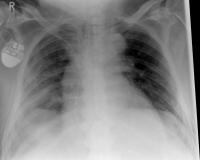

Rippenserie re1